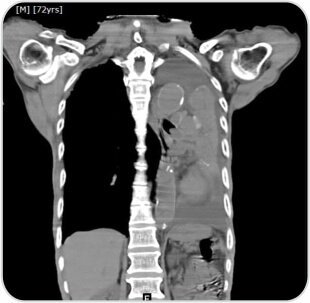

72 years old male, reformed smoker now presented with cough, shortness of breath and haemoptysis.

Pre procedure CT image showing collapsed left lung with occluded left main bronchus